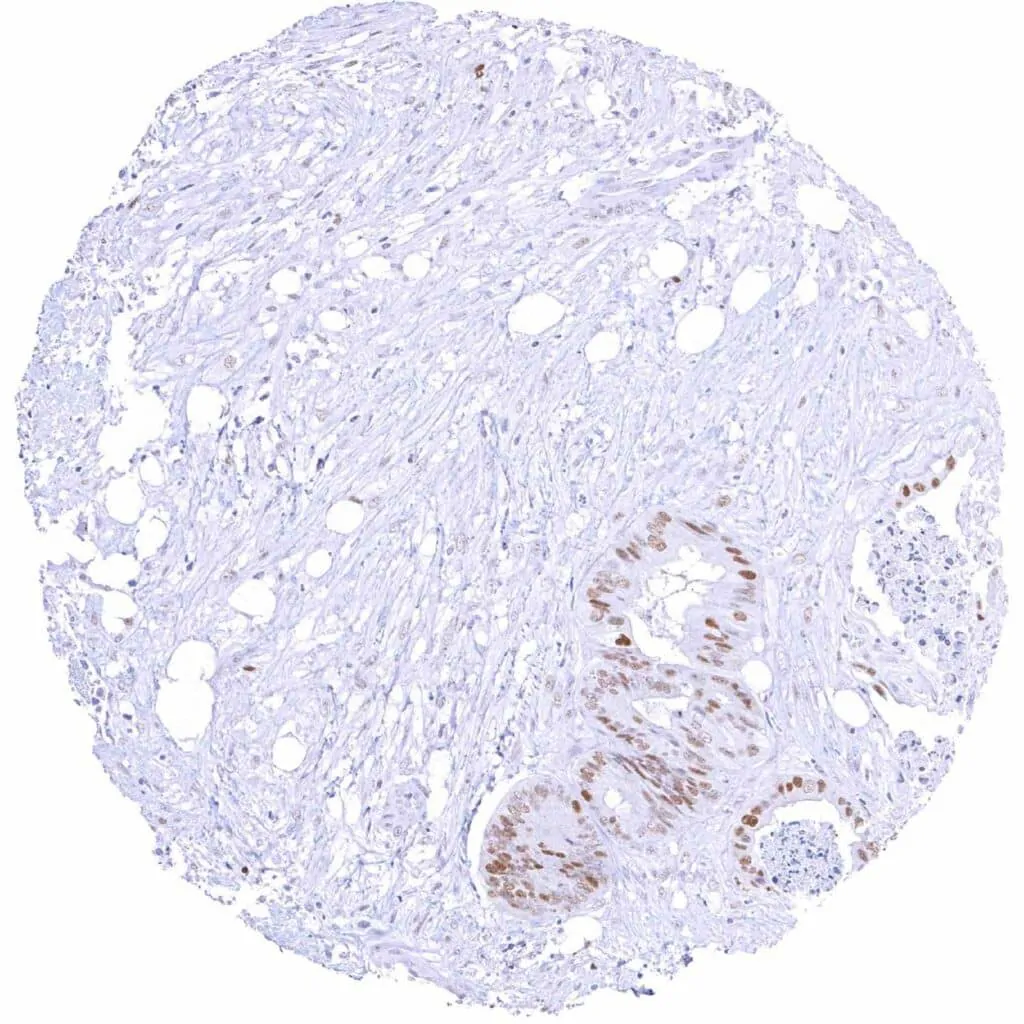

Breast – Invasive breast cancer of no special type (NST) with faint Cyclin E1 immunostaining of few tumor cells